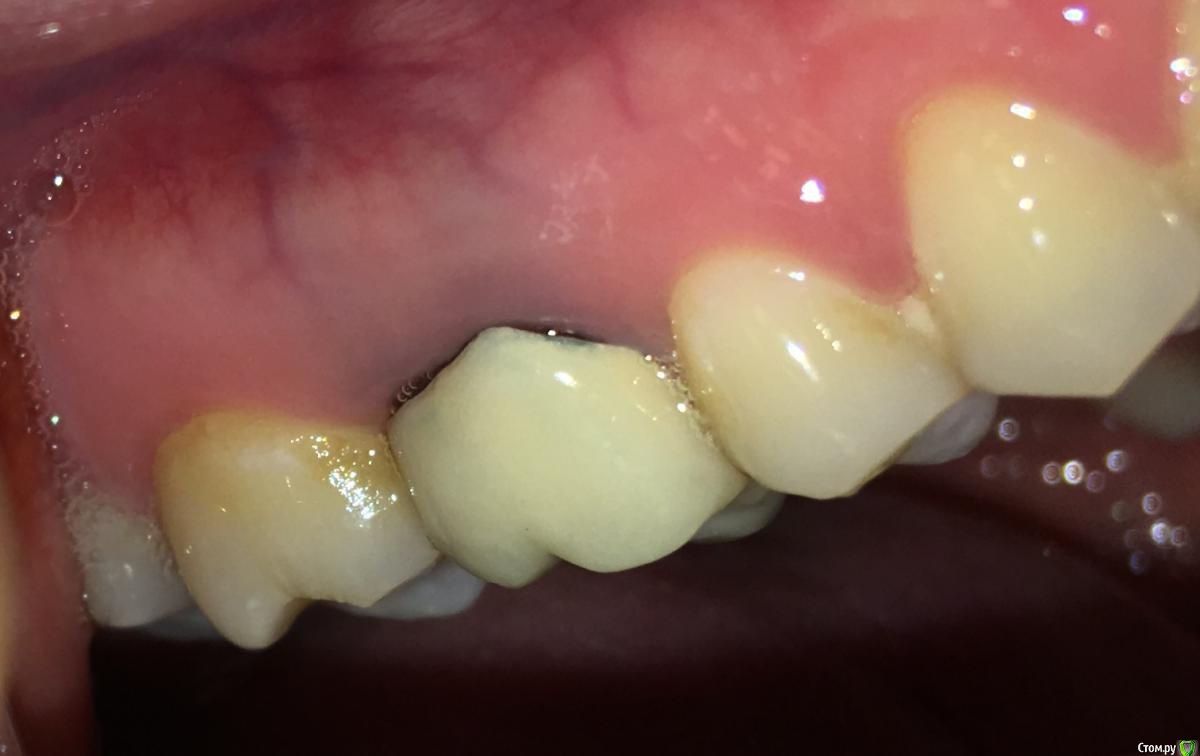

MichaelV Опубликовано 10 ноября, 2019 Автор Поделиться Опубликовано 10 ноября, 2019 (изменено) Сняли повторный слепок с ниткой, сделали новую коронку, выглядит так: https://cloud.mail.ru/public/8RrK/2uRCNHkwp (выложил несколько фото в облако, т.к. на форум больше одной уже не влезает). Изменено 10 ноября, 2019 пользователем MichaelV Ссылка на комментарий